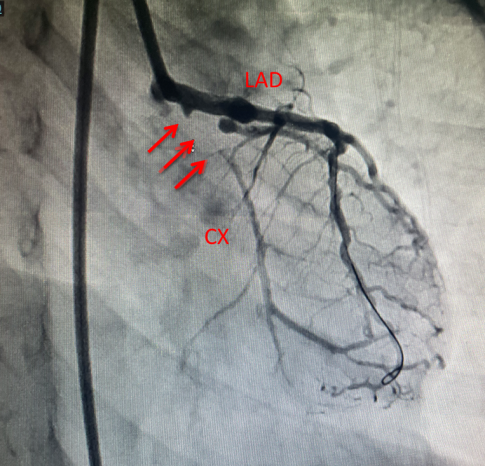

经过充分准备,11月10日,涵涵实施了冠状动脉闭塞再通及球囊扩张术。由于涵涵仅6岁,手术难度极大,但治疗小组制定了缜密的方案,历经1个半小时的手术,完美的完成了血运重建,手术后造影显示闭塞的冠状动脉完好显影(图2,图3),未见夹层及假性动脉瘤形成,整个手术操作一气呵成。

图2. 2.5mm*30mm的药物球囊(箭头)进行扩张